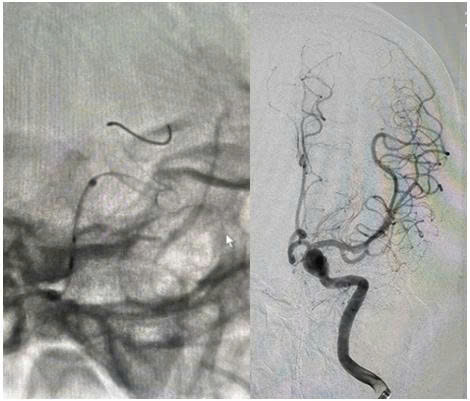

Ngay khi nhập viện, các bác sỹ nghi ngờ bệnh nhân có bất thường hệ thống mạch máu não nên đã chỉ định chụp cắt lớp vi tính mạch máu não cho bệnh nhân. Kết quả hình ảnh chụp cắt lớp vi tính mạch máu não cho thấy, bệnh nhân có túi phình lớn ở động mạch cảnh trong trái, kích thước khoảng 10 x 8 x 6 mm, khu trú tại đoạn động mạch mắt.

Hình ảnh túi phình lớn ở động mạch cảnh trong trái trên CLVT mạch máu não

Quá trình can thiệp được thực hiện qua động mạch đùi phải theo phương pháp Seldinger. Bệnh nhân được chụp mạch não để đánh giá chính xác túi phình. Ê-kíp đã đặt thành công stent chuyển dòng kích thước 4,25 × 20 mm qua cổ túi phình động mạch cảnh trong trái đoạn động mạch mắt. Hình ảnh sau can thiệp cho thấy stent áp sát thành mạch, che phủ hoàn toàn cổ túi phình, giảm rõ rệt dòng máu vào túi phình, đồng thời đảm bảo tưới máu não tốt, tuần hoàn não trước đạt TICI 3.